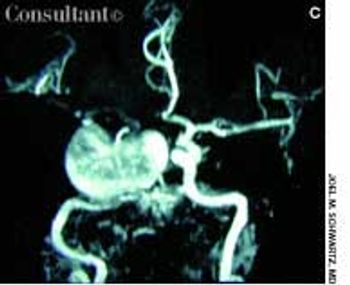

Headache and vomiting suddenly developed in a 41-year-old woman who was 16 weeks pregnant. The next day, she suffered an episode of tonic-clonic seizures associated with a 15-minute loss of consciousness.